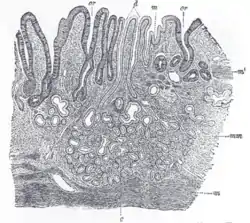

![]() Gastric glands shown at c and their ducts at d | |

Gastric glands are mostly exocrine glands[2] and are all located beneath the gastric pits within the gastric mucosa—the mucous membrane of the stomach. The gastric mucosa is pitted with innumerable gastric pits which each house 3-5 gastric glands.[3][4] The cells of the exocrine glands are foveolar (mucus), chief cells, and parietal cells. The other type of gastric gland is the pyloric gland which is an endocrine gland that secretes the hormone gastrin produced by its G cells.

There are millions of gastric pits in the gastric mucosa and their necessary narrowness determines the tubular form of the gastric gland. More than one tube allows for the accommodation of more than one cell type. The form of each gastric gland is similar; they are all described as having a neck region that is closest to the pit entrance, and basal regions on the lower parts of the tubes.[8] The epithelium from the gastric mucosa travels into the pit and at the neck the epithelial cells change to short columnar granular cells. These cells almost fill the tube and the remaining lumen is continued as a very fine channel.